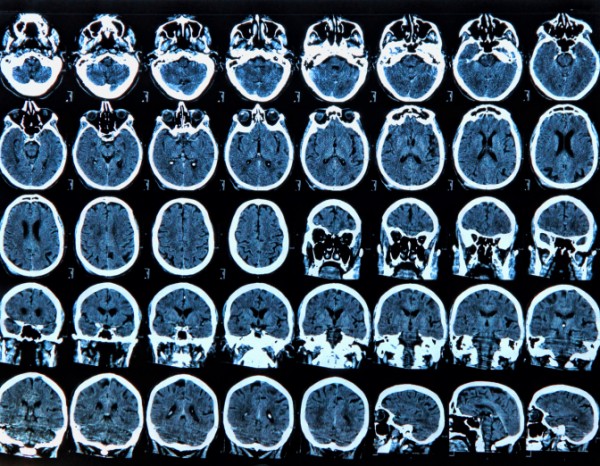

La malattia di Alzheimer, spesso definita anche come “morbo” rappresenta la forma di demenza degenerativa più frequente in assoluto: in Italia ne soffrono circa 500.000 persone e secondo le statistiche più recenti quasi 27 milioni di individui in tutto il mondo (prevalentemente donne). Non a caso è considerata alla stregua di una epidemia del nuovo millennio a cui prestare particolare attenzione in termine di ricerca scientifica e non solo, anche a causa del crescente numero di casi ogni anno, oltre che dei costi in termini socio economici che comporta.Ma quali sono le cause?